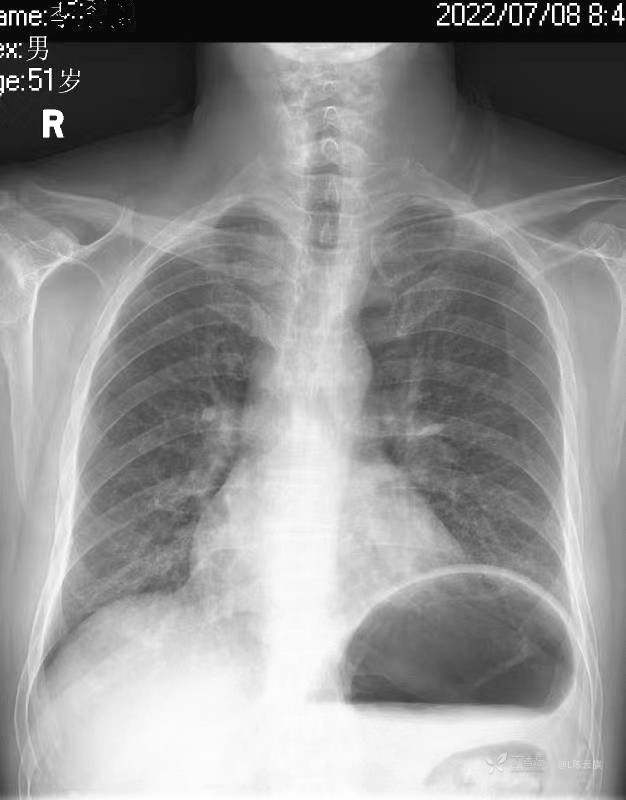

华夏览雄 达人已点赞1、患者男,51岁,精神病长期住院患者,主要病史只有时不时觉得腹部不适,其他不详。系列胸片为定期胸部检查。